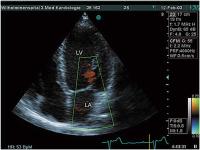

Abbildung

Mitralinsuffizienz

Abbildung 1: Apikaler Vierkammerblick, inkomplette Schlußstellung der Mitralklappe, diastolisches Regurgitationssignal bei AV-Block III (LA = linker Vorhof, LV = linker Ventrikel))